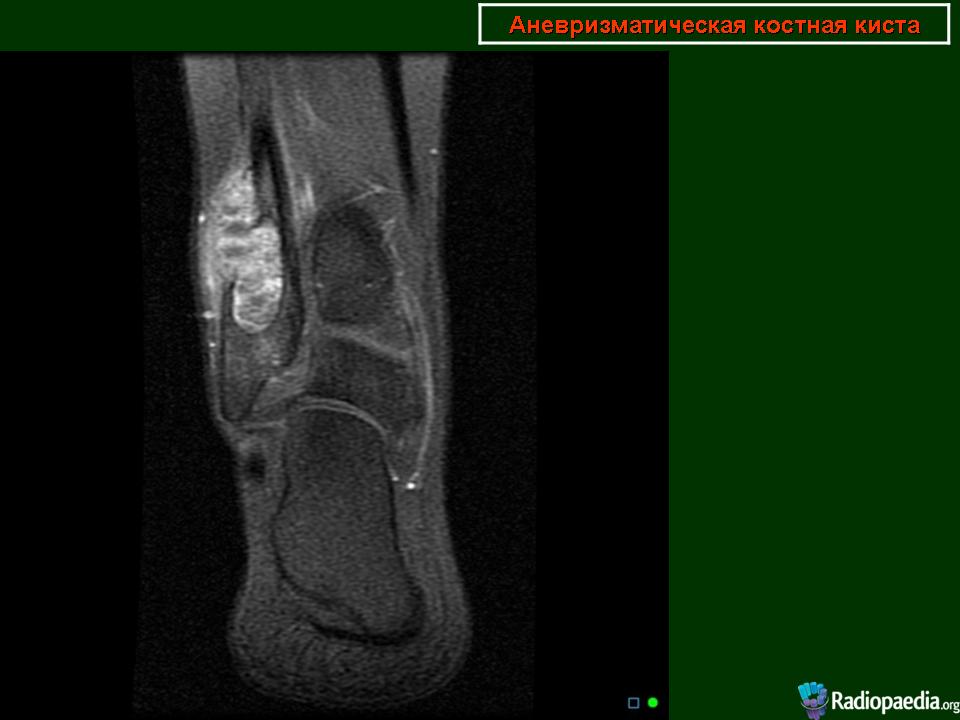

Мужчина с жалобами на периодические боли в голеностопном суставе.Спортсмен.Проходил КТ-исследование 2 года назад в Корее, принес снимки, но заключение письменного почему-то не получил.На словах сказали, что "какая-то опухоль".Его родственник -мой коллега_ попросил провести рентгенографию сустава, после чего направил на МРТ.Рентгенограммы по тех. причинам буду чуть позже))))

По поводу случая-пока склоняюсь к аневризматической костной кисте.Может быть и неправа, но узнаю результаты похода пациента в онкодиспансер.

Я за кисту. Но на МРТ не нравиться , что процесс выходит за пределы кости.